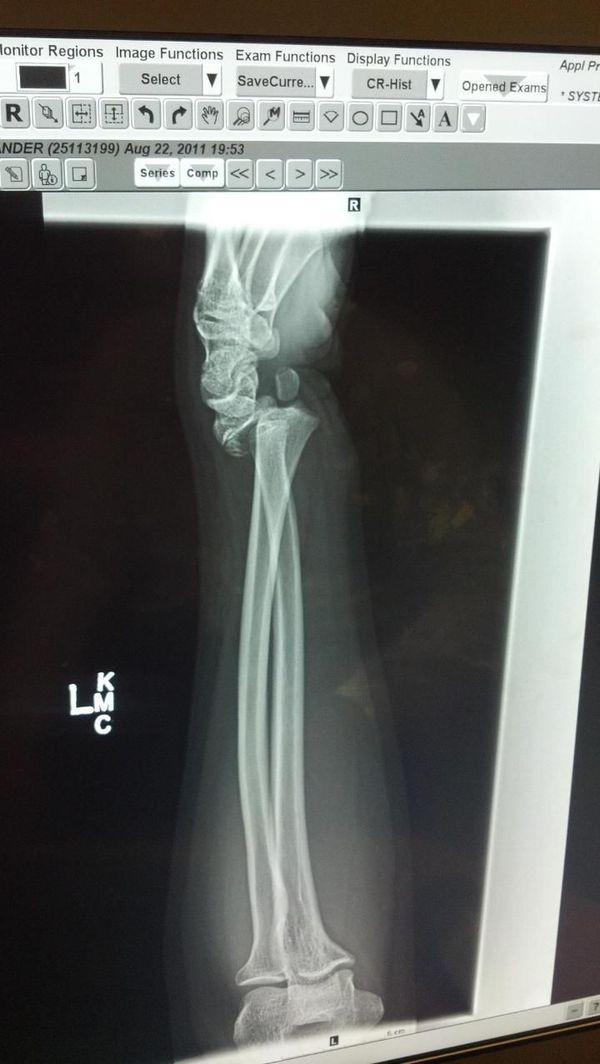

From medizzy.com

Football injury. Fractured and dislocated wrist Can U Play Football With A Fractured Wrist Broken wrist — wrist fractures in football typically happen when a player falls onto an outstretched hand or direct impact on the wrist from a hard object such as a helmet, shoulder pads, or cleats. We delve into safety precautions, risks involved, and. While there's no explicit rule against playing with a broken wrist, precautions are essential. These are also. Can U Play Football With A Fractured Wrist.